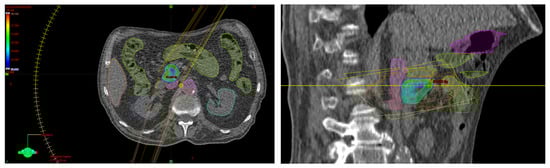

3. Second Case